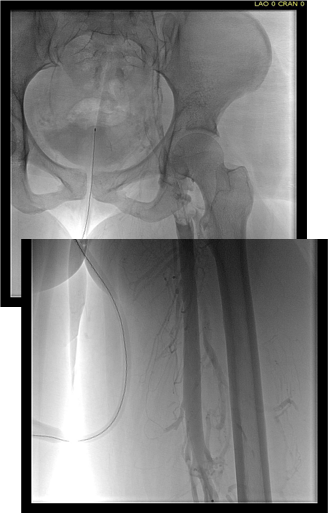

Examination revealed a fit and trim man in his 70’s in no apparent distress. He had bilateral leg edema that was moderate with small superficial and tender ulcers of the right posterior distal calf. Pulses were normal. He was taken to our hybrid suite and venography from femoral vein access in the proximal thigh in the supine position revealed his right and left iliac venous systems to be occluded (below figures).

right initial venogram

Right injection from femoral sheath showing occluded iliac vein with collaterals

left initial venogram.png

Left injection

Wire access into the iliac systems was performed with Glidewire and Glidecatheter periodic venography to confirm that I had not exited the vein. Unlike the arterial system, extravasation from being extravenous does not have the consequence of bleeding, hematoma development, and pseudoaneurysm formation because of the low pressure, but it can be a long procedure and uncomfortable as well so these are done under general anesthesia.

intervention fig 1.png

Advancing wire and sheath into iliac vein, crossing filter resulted in extravasation of contrast

Once position confirmed to be in the iliac vein, the vein was dilated to allow for greater ease of movement. In the case of the uncrossable filter, I switched to access from above via a right internal jugular vein access.

intervention fig 2.png

Dilating vein (left) for greater mobility, and crossing from above (R. IJV access)

Once the wire crossed into the iliac vein from above, it was captured and brought out. While ballooning by itself is inadequate for revascularization, it greatly eases wire capture and on the right, it was done simply by driving the wire from above into the sheath. Wire capture wins access across the iliocaval and IVC filter occlusion from below.

intervention fig 3.png

Wire passage across IVC filter into right and left systems